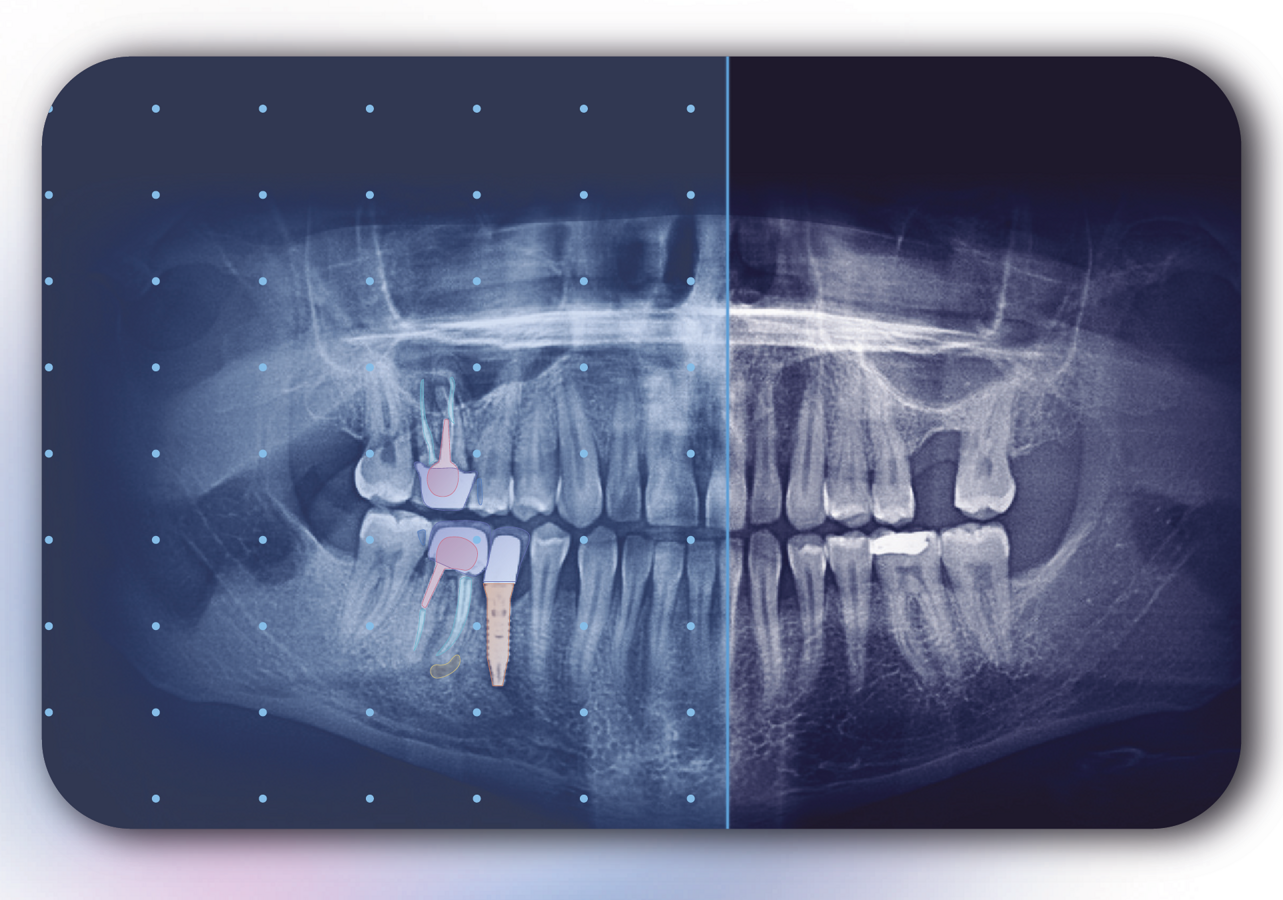

Allisone brinda claridad a los pacientes, lo que puede aumentar su comprensión, confianza y cumplimiento del tratamiento. (Imagen: Allison)

Allisone es una herramienta de comunicación con el paciente que utiliza IA para resaltar elementos de las radiografías dentales que permiten a los pacientes visualizar y comprender la atención dental que necesitan. (Imagen: Allison)

Allisone es un software que utiliza tecnología de inteligencia artificial, aprendizaje profundo y visión por computadora, mediante la cual reconoce elementos en una radiografía dental de la boca. Los resultados se visualizan mediante una interfaz simple e intuitiva que ayuda a los dentistas a mostrar los elementos en la radiografía a través de un código de colores.

El propósito principal de esta funcionalidad es apoyar visualmente la explicación del dentista sobre los tratamientos que necesita paciente. Allisone produce instantáneamente el informe radiográfico, el plan de tratamiento y las ilustraciones y agrega hojas educativas basadas en el tratamiento seleccionado por el dentista. Estos elementos se pueden enviar al paciente o imprimir para dárselo en mano. Allisone se puede integrar con otros softwares comerciales y es accesible desde cualquier computadora en la consulta o clínica.